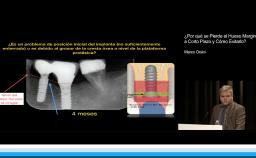

En esta conferencia, la Dra. Iria López habla acerca de las complicaciones que pueden presentarse en prótesis diseñadas con cantiléver. La Dra López lleva su exposición de una forma organizada, en la que primero, fundamenta la relevancia del tema y la frecuencia con la que este tipo de tratamientos se llevan a cabo. Posteriormente hace un análisis tanto de las diferentes circunstancias en las que un cantiléver puede ser utilizado y el tipo de complicaciones protésicas que se pueden presentar. Muestra una excelente selección de artículos que brindan evidencia no solo de las complicaciones protésicas, sino incluso del comportamiento biológico de los implantes que soportan este tipo de prótesis.

• describir las principales complicaciones que una prótesis diseñada con cantiléver puede llegar a presentar, así como las alternativas para prevenirlas y/o tratarlas